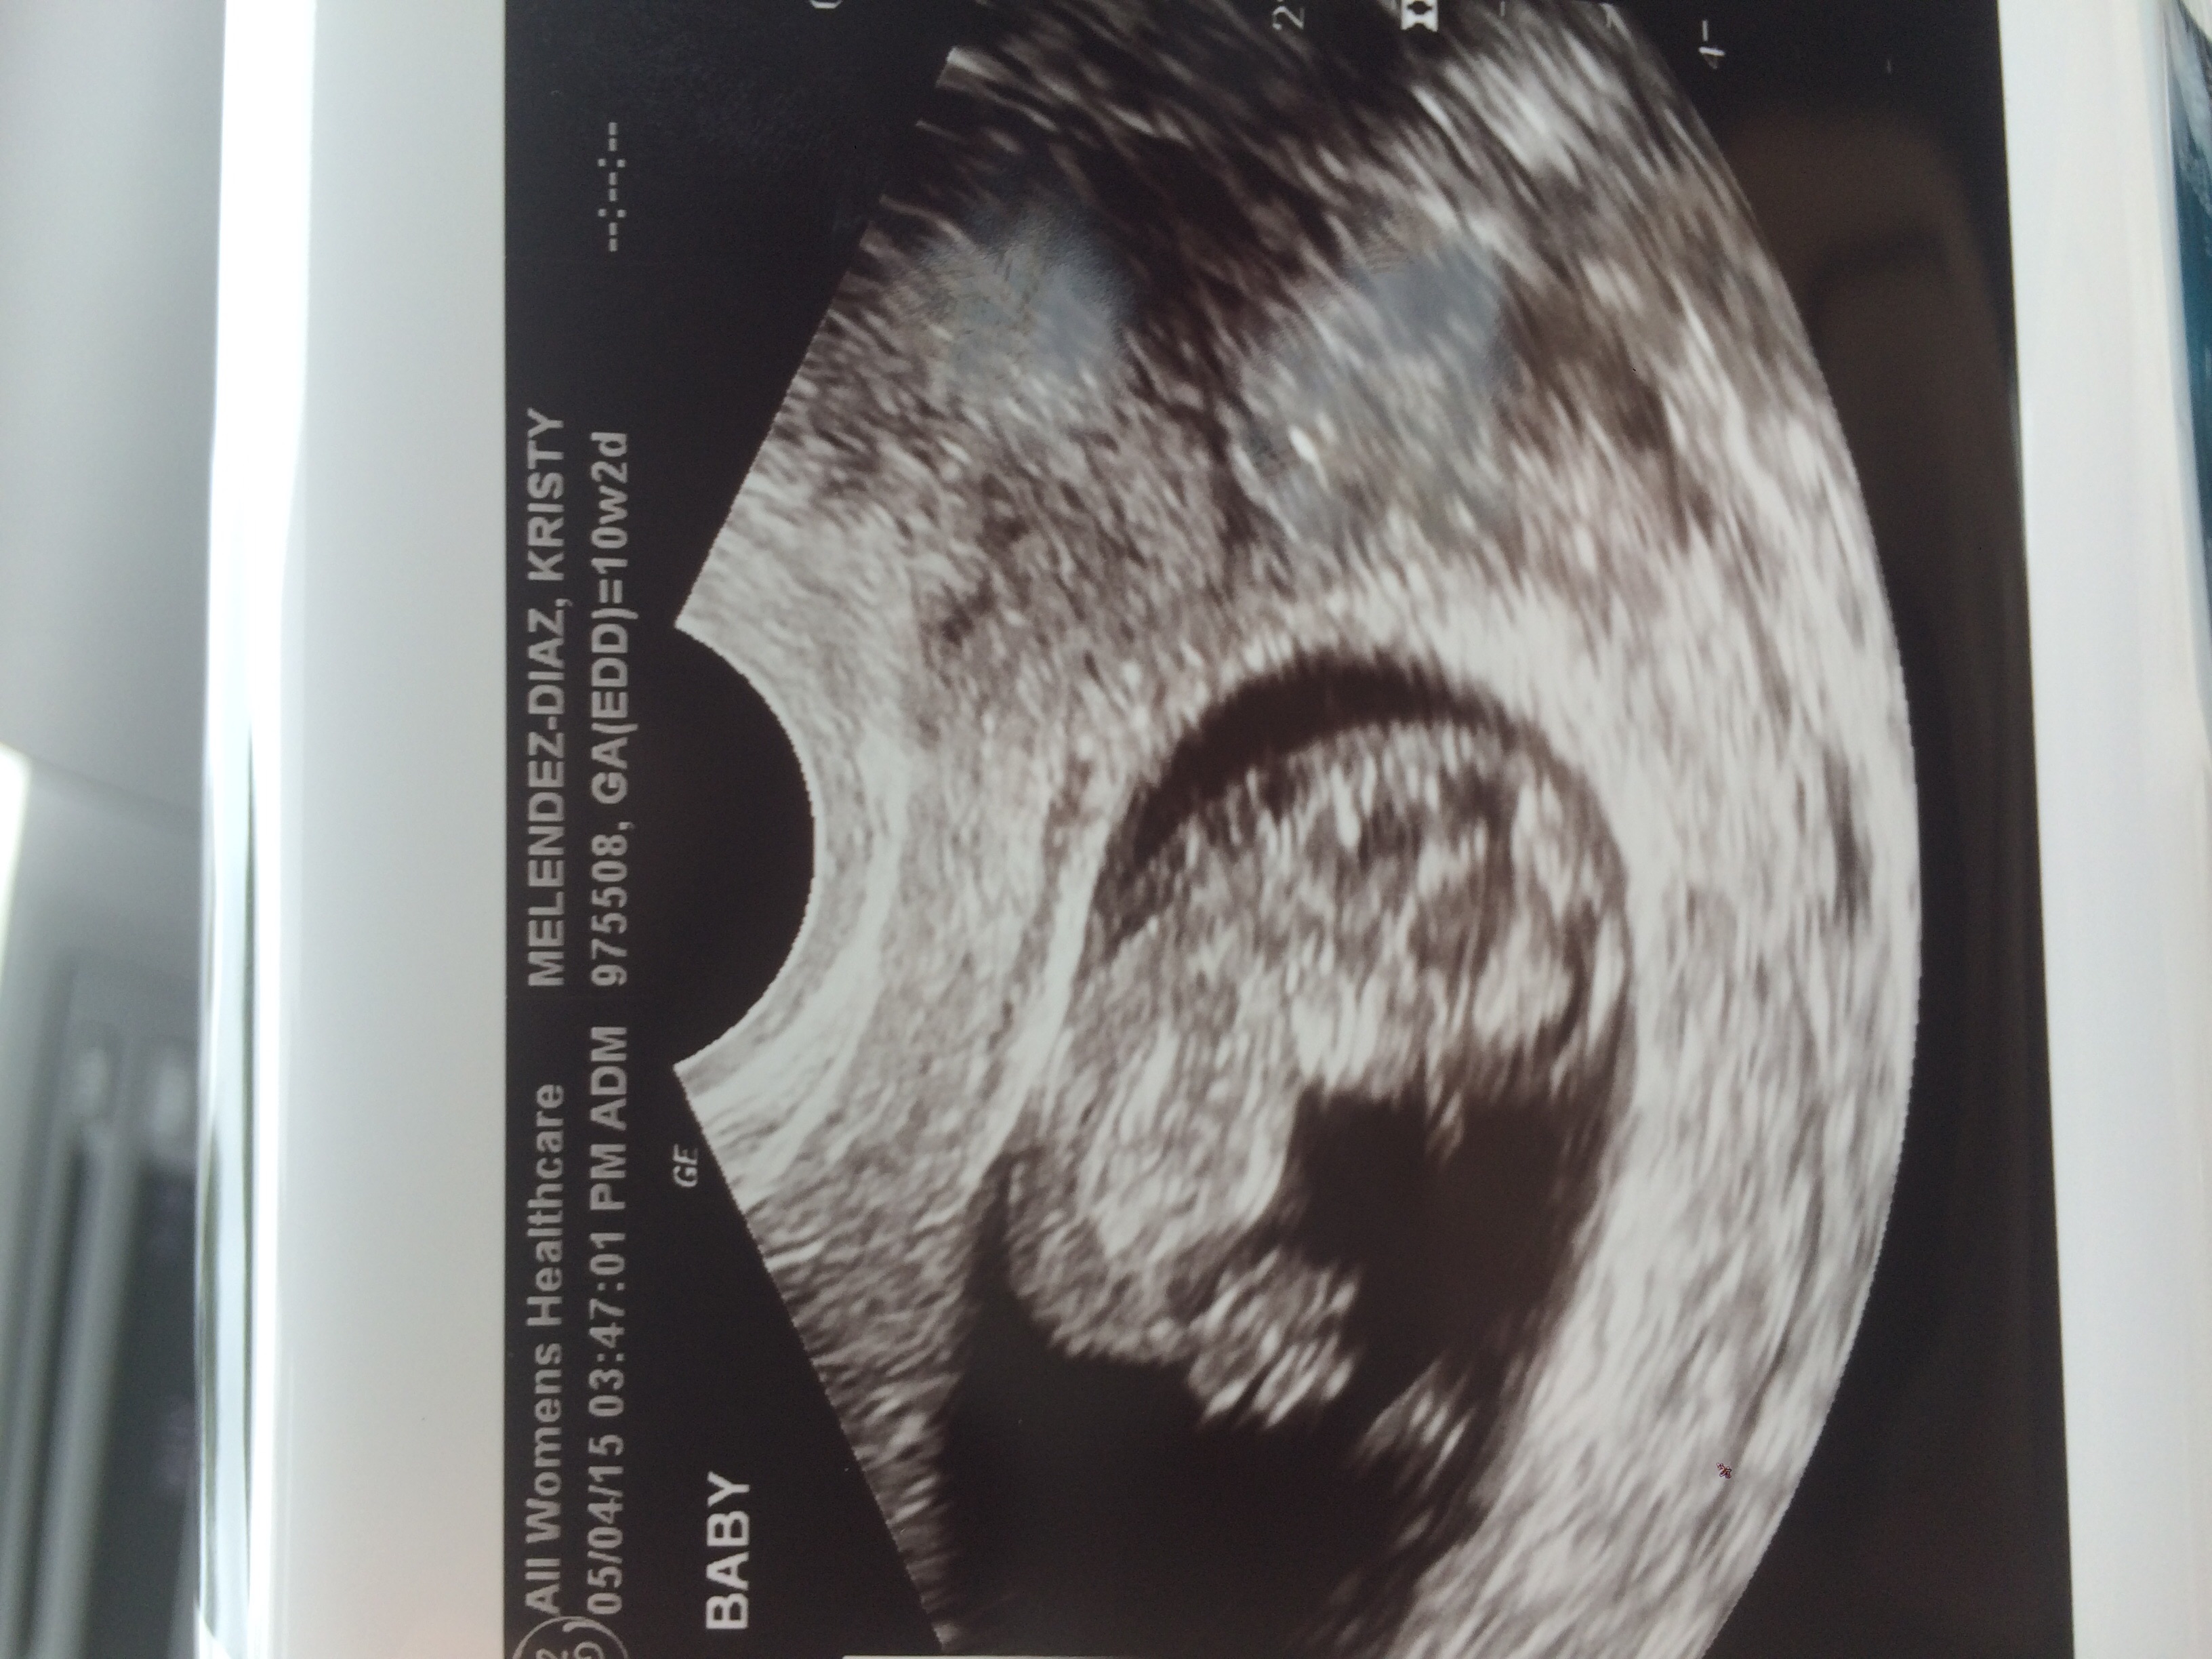

10 weeks 4 days yesterday.... Was waving and squirming all over... HR was 173.... So amazing... Get genetics test results and gender back in 7-10 business days!